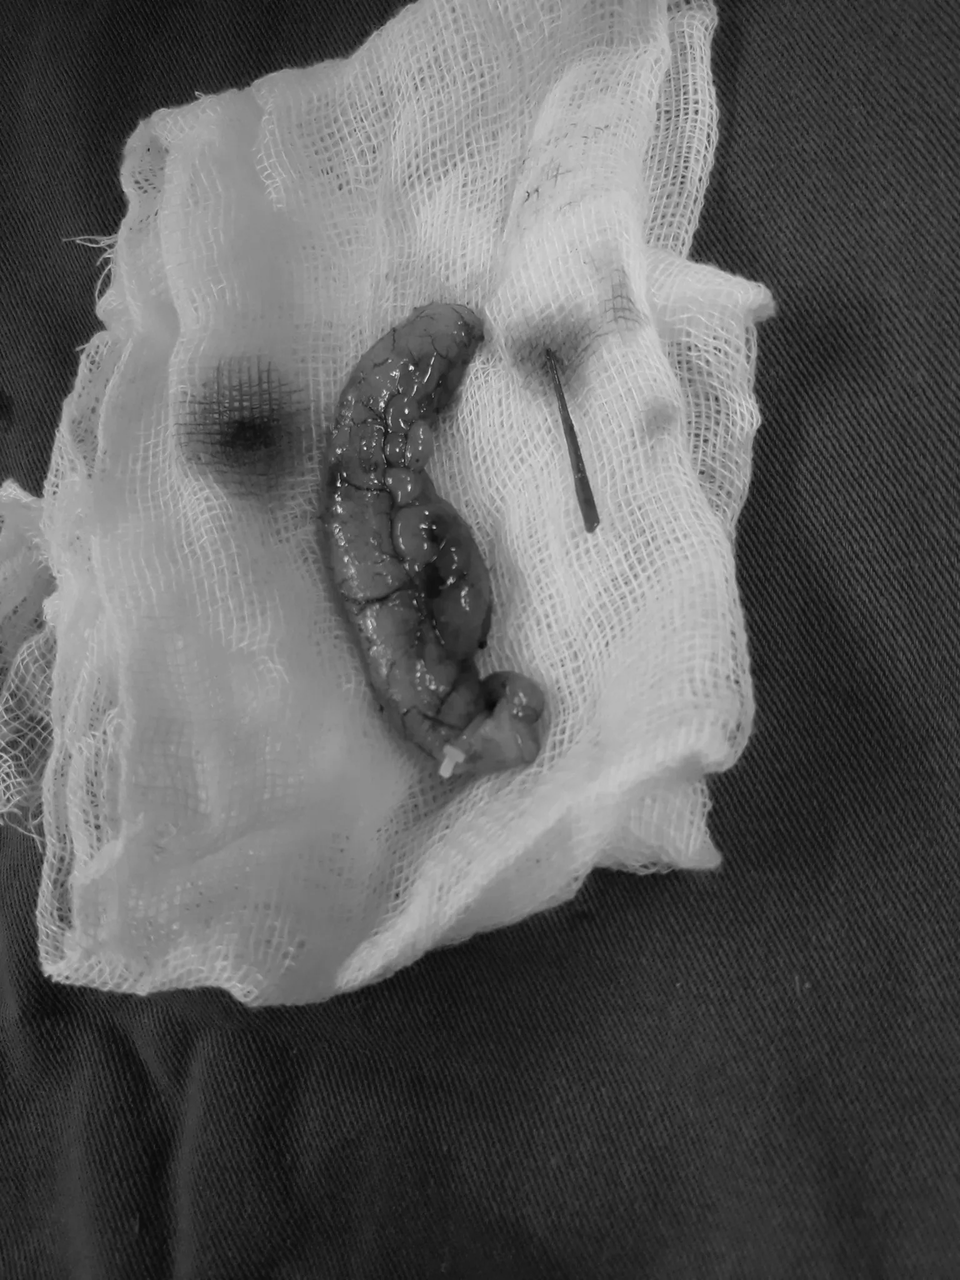

Khi tiến hành phẫu thuật nội soi cắt ruột thừa cho bệnh nhân, các bác sĩ phát hiện "thủ phạm" là một chiếc tăm nhọn đâm xuyên thủng ruột, thòi tăm ra ngoài.

Với trường hợp bệnh nhân này, dị vật là que tăm chui vào lòng ruột thừa và gây thủng ruột thừa, là trường hợp vô cùng hiếm gặp.

Trong trường hợp này, là do bệnh nhân vô tình nuốt phải dị vật. Dị vật tăm nhọn đã có một quá trình di chuyển vô cùng phức tạp. Sau khi đi qua miệng vào, dị vật đi xuống thực quản, dạ dày, tá tràng, ruột non sang manh tràng và chui qua gốc ruột thừa có đường kính rất nhỏ khoảng (2-4mm) nằm trong lòng ruột thừa và chọc thủng ruột thừa chui một nửa ra khoang bụng.